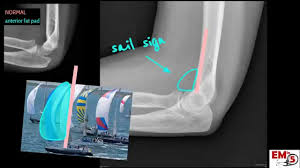

10+ Elbow Anatomy Xray. Elbow injuries have characteristic appearances. This is an online quiz called elbow xray anatomy.

Soft tissue abnormality is often the only evidence of bone injury.